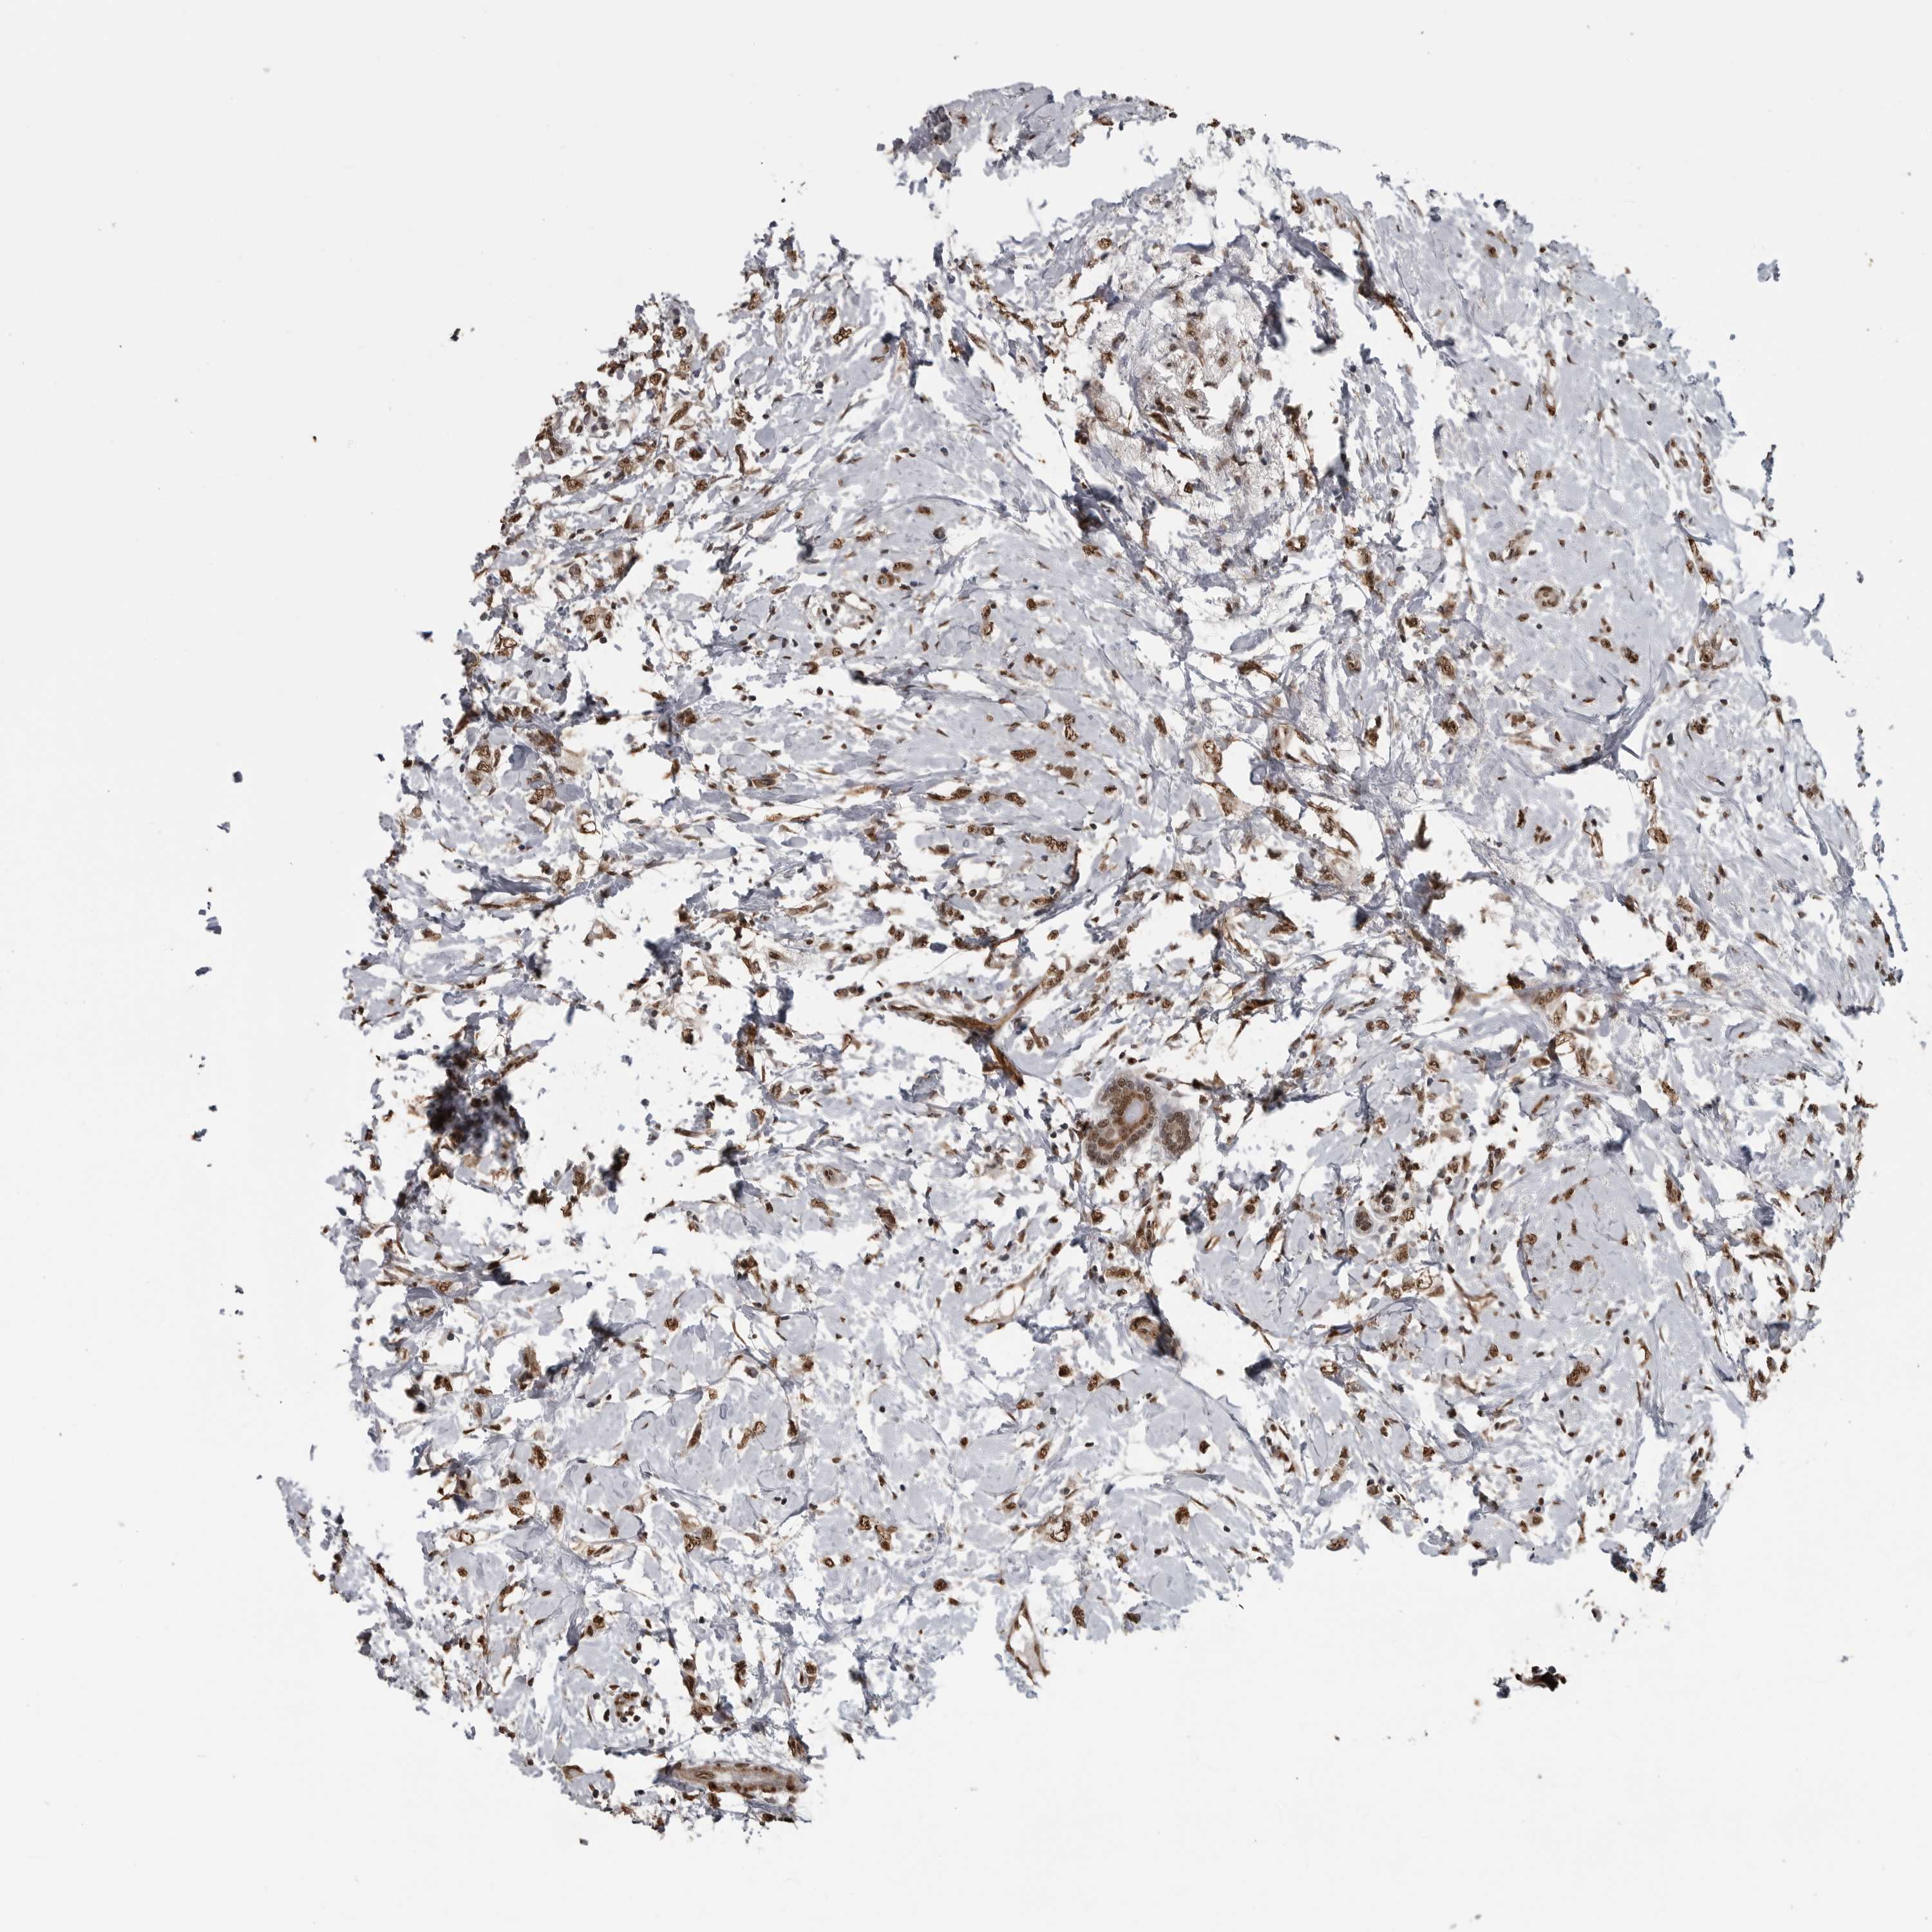

CANCER BREAST CANCER Show tissue menu

BRCA TCGA BRCA VALIDATION PROTEIN EXPRESSION

ANTIBODIES

AND

VALIDATION